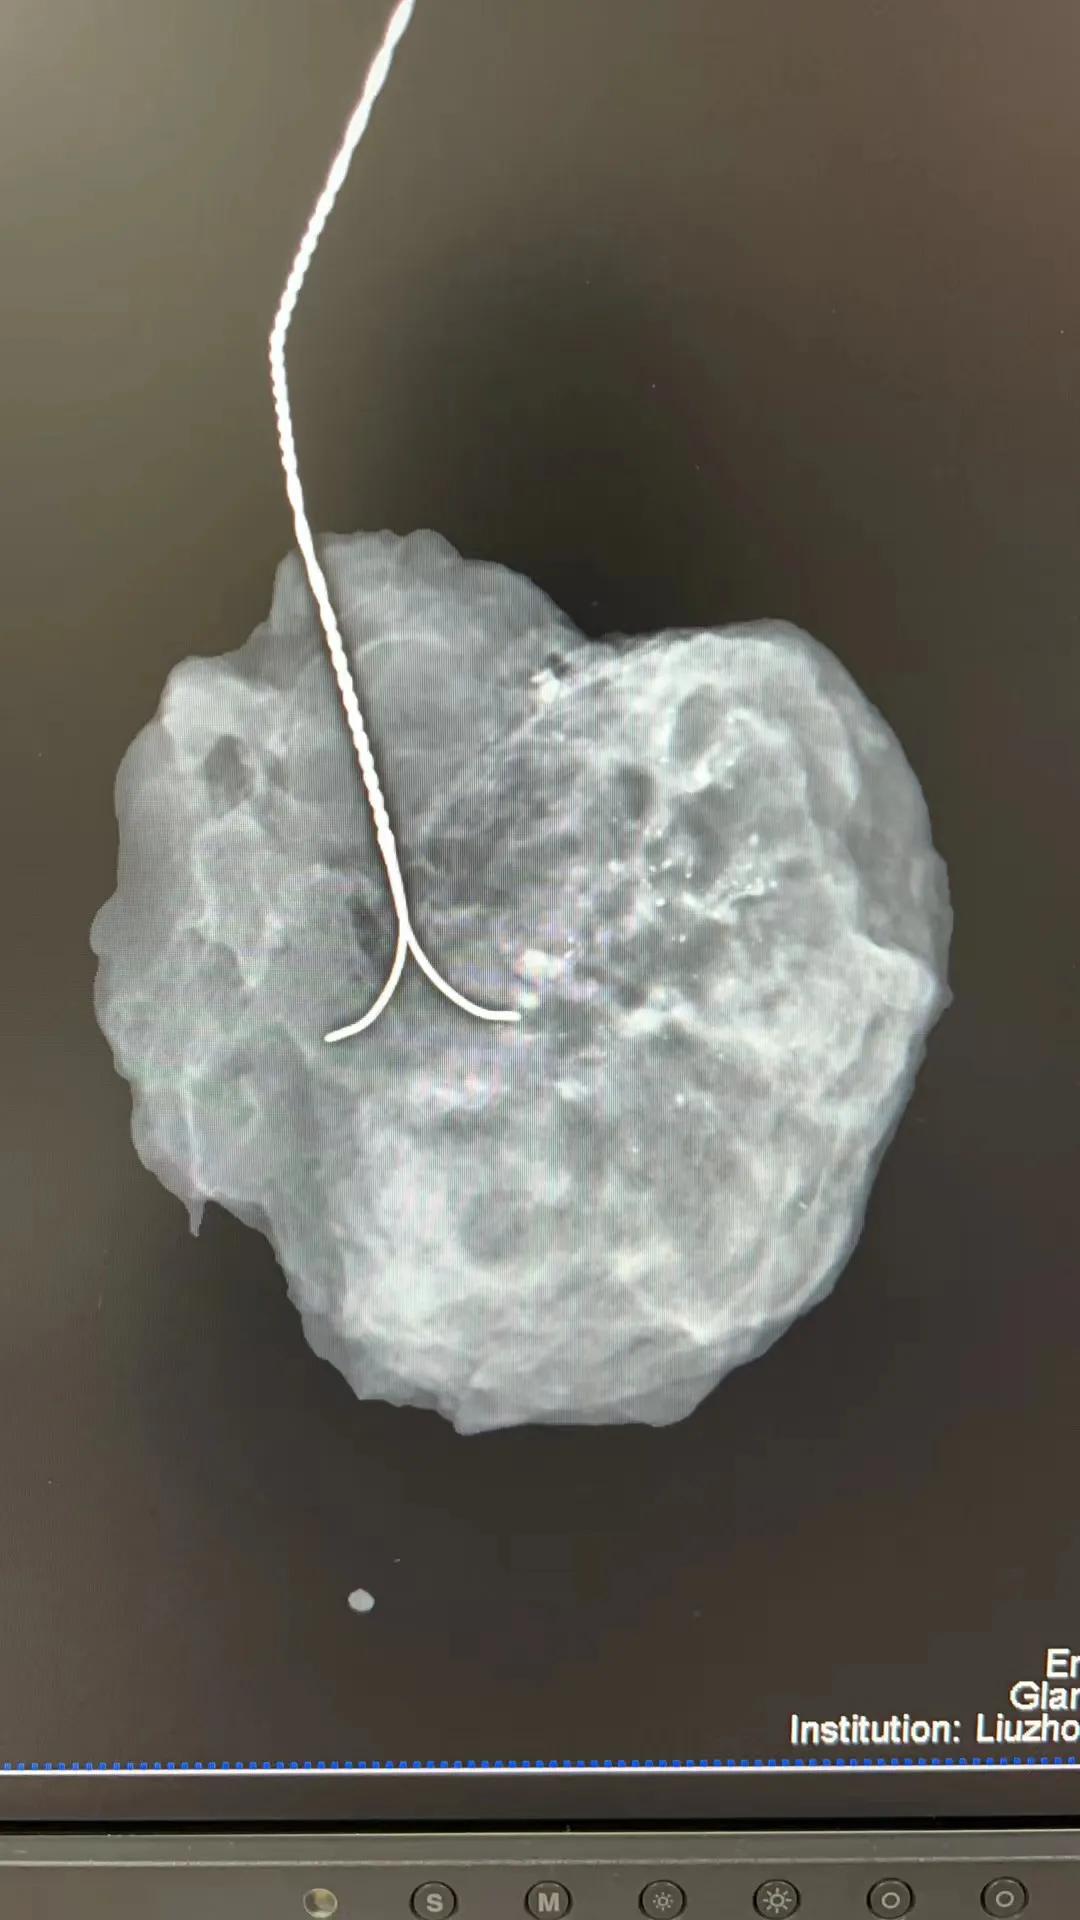

术中将切除的标本送至钼靶室检查,图中小小的白点就是钙化灶

术中标本再次送至钼靶室检查,确保可疑恶性的钙化灶被切除后再送病理检查